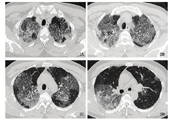

患者,男性,58岁,因"咳喘伴畏寒1周"于2020年1月17日入同济大学附属上海市第四人民医院呼吸科就诊。患者1周前无明显诱因出现咳嗽,活动后稍有气喘,无发热、咳血,无胸痛、晕厥、黑朦、心慌。血常规示:白细胞计数5.47×109个/L,血红蛋白浓度121 g/L,血小板计数168×109个/L,淋巴细胞百分比19.6%,中性粒细胞百分比72%,C反应蛋白浓度9.89 mg/L。胸部CT示:两肺多发磨玻璃影,两肺上叶明显,考虑炎性病变(见图1)。甲乙流病原体快速检测:阴性。门诊予以头孢西丁和左氧氟沙星抗炎治疗,后患者于急诊继续用药近2周。患者于1月31日再次于呼吸科门诊复诊,自觉仍有咳嗽,活动后气促明显。复查血常规示:白细胞计数8.7×109个/L,淋巴细胞百分比10%,中性粒细胞百分比83.9%,C反应蛋白浓度159.25 mg/L。甲乙流病原体快速检测:阴性。胸部CT示:两肺大片炎症,较2020年1月17日明显进展,病毒性肺炎可能(见图2)。患者否认发病前14 d旅游外出史,否认接触疫区有发热或呼吸道症状的患者,否认聚集性发热。自诉1月19日有外出打麻将行为,否认牌友有发热,但牌友的具体流行病学史不详。因此考虑患者有感染新型冠状病毒肺炎可能,予以发热门诊留观病房隔离观察,并采集上呼吸道、下呼吸道、血液标本进行新型冠状病毒核酸检测。